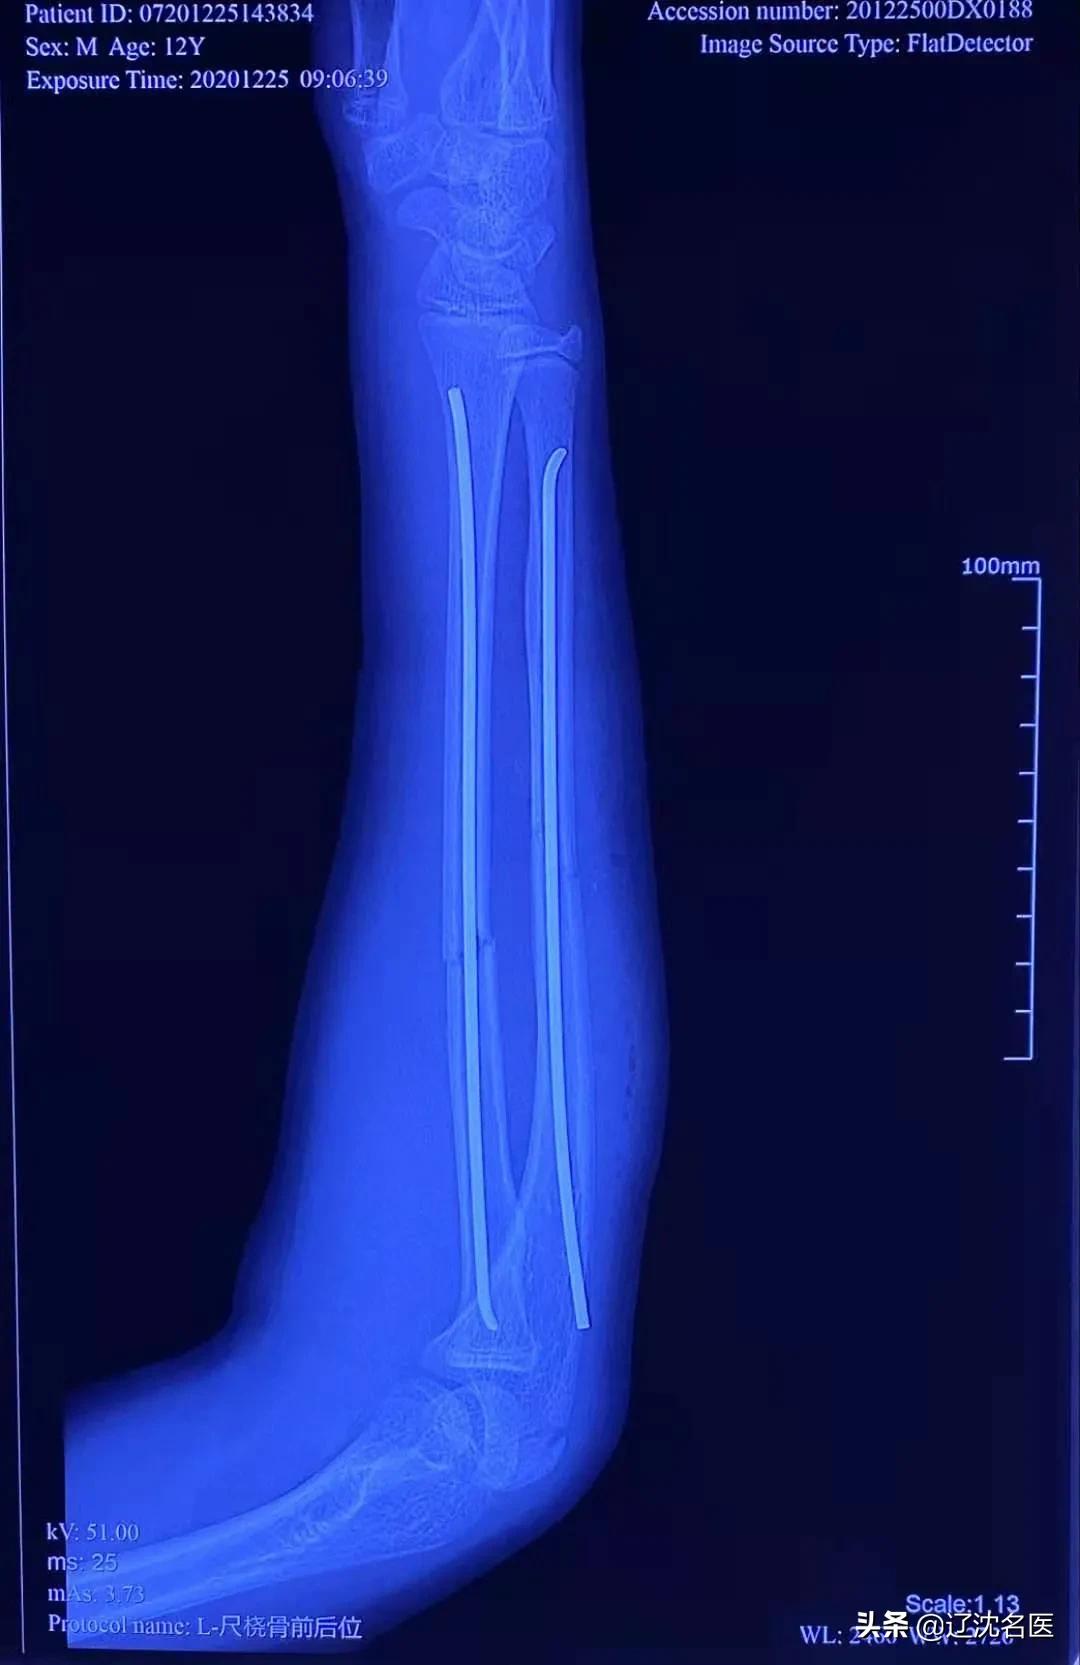

患儿在臂丛麻醉下,经过蔡振存医师治疗小组精心准备和仔细操作,仅在患儿的腕部和肘部各做一个长约5mm的切口,C型臂透视下分别从桡骨远端及尺骨近端各植入一根的弹性髓内钉,然后利用弹性钉远端钩弯特点进行撬拨骨折复位,利用弹性钉弹力支撑特点予以骨折固定。30分钟后,手术顺利完成。

(术后X线:骨折复位良好,弹性钉固定稳定)